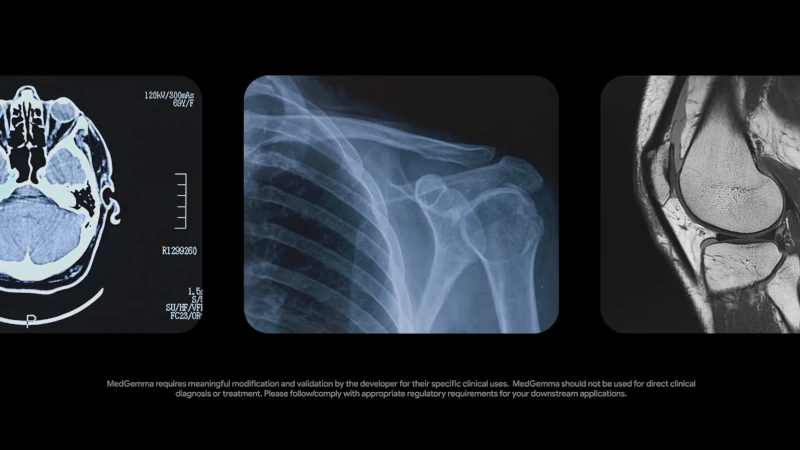

- MedGemma 4B Multimodal โมเดลสำหรับงานแยกแยะภาพ (image clarification) โดยเฉพาะ ใช้อ่านภาพถ่ายรังสี ภาพเอ็กซ์เรย์ ภาพจากเครื่องสแกนต่างๆ ภาพถ่ายผิวหนัง ฯลฯ

Introducing MedGemma, our most capable open model for multimodal medical text and image comprehension. 🩻MedGemma is available now as part of Health AI Developer Foundations → https://t.co/GfJkvBHjTF pic.twitter.com/uEIbwkjr4l